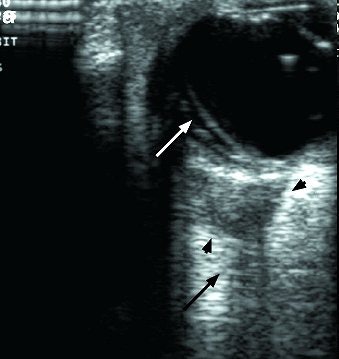

![]() |

| A cone-shaped rhabdomyosarcoma (arrowheads) is seen in the orbit behind the eyeball. The optic nerve (black arrow) is partially encased by the tumor. Note the retinal detachment (white arrow) in the eye. The patient was a five-year-old child. Ultrasound imaging made it unnecessary to perform MRI, which would have required sedation. |